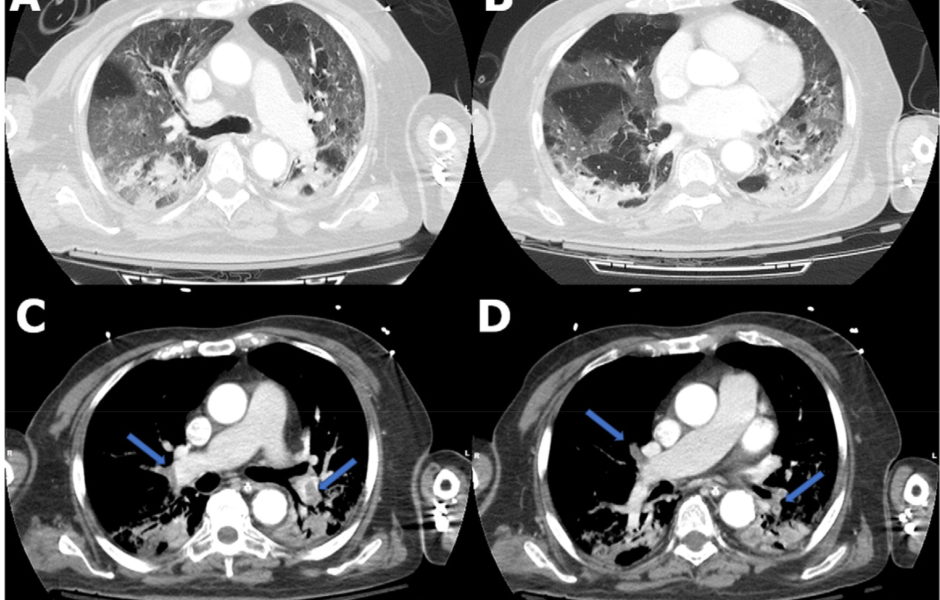

Covid 19 Ce Que Les Autopsies Nous Apprennent Sur Les Caillots Sanguins Et Embolies Pulmonaires Realites Biomedicales

www.lemonde.fr

Embolie Pulmonaire Et Coronavirus L Etude Du Pr Delabrousse Mise En Avant Au Niveau Mondial Macommune Info

www.macommune.info

Study Finds Link Between Pulmonary Embolism And Covid 19 Ge Healthcare

www.gehealthcare.com